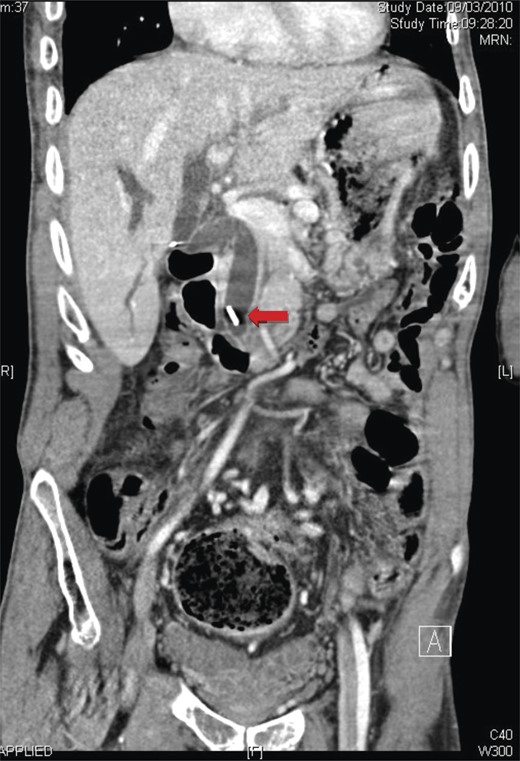

Laboratory tests revealed elevated liver function tests: ALP 285 U/l, ALT 465 U/l, GGT 669 U/l with a normal bilirubin. Magnetic resonance cholangiopancreatography demonstrated marked dilatation of the common bile duct to 15 mm (Fig. 1). A surgical clip was noted in the distal common bile duct, presumed to have migrated from the cystic duct, which it had been used to close 9 years previously.

A coronal view of magnetic resonance cholangiopancreatography showing the presence of a surgical clip and common bile duct dilatation.